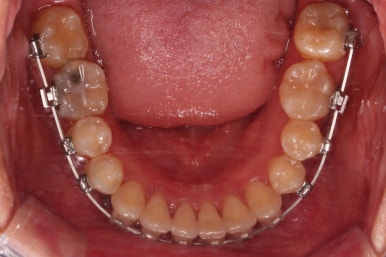

초진 시 입안의 모습입니다.

이미 썩어서 부러진 치아도 몇 개 보이고요.

많이 삐뚤어진 치아쪽은 양치가 힘들어 이미 많이 썩어 있는 상태에 덧니쪽은 잇몸도 많이 내려간 상태였습니다.

말그대로 교정치료 뿐만 아니라 전반적인 치료가 필요한 상황이었습니다.